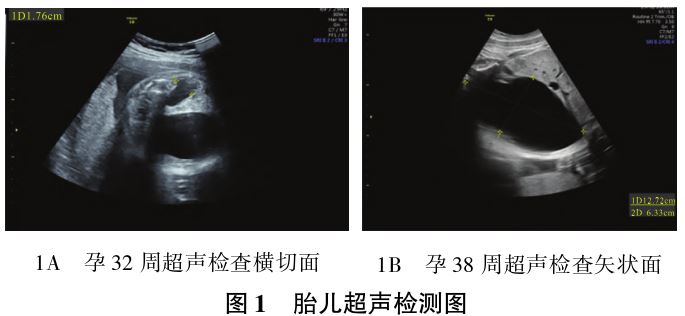

患者,28岁,G1P0,因孕38+1周,羊水进行性增加1+月,于2020年12月2日就诊于四川大学华西第二医院。孕早期于本院建卡产前检查,孕早期无阴道流血、流液,无毒物、射线接触史。孕早期唐氏筛查提示低风险,孕中期唐氏筛查:游离血β-人绒毛膜促性腺激素(β-hCG)轻度升高(2.65 U/L),遂行无创产前基因检测(NIPT)提示低风险,胎儿颈项透明层(NT)、胎儿系统产前超声、胎儿心脏超声检查未见明显异常。孕29周常规产前超声检查首次提示:胎儿双肾集合系统分离,胎儿膀胱大小约6.6 cm×3.7 cm×5.6 cm,反复动态观察未见明显缩小,羊水指数及羊水深度均在正常范围。孕32周复查胎儿泌尿系统针对性超声检查提示:胎儿膀胱大小8.9 cm×5.2 cm×5.4 cm,半小时后膀胱大小8.1 cm×4.3 cm×4.9cm,右肾集合系统分离0.70 cm,肾皮质最薄处厚约0.42 cm,左肾集合系统分离1.76 cm(见图1A),伴肾小盏扩张,肾皮质最薄处厚约0.16 cm。双侧输尿管未见明显扩张。羊水深度达8.8 cm,羊水指数达22.8 cm。于本院遗传科咨询建议行羊水穿刺,但患者因个人因素错过检测时机,患者及家属选择继续妊娠

并定期产检。孕晚期定期复查针对性彩超检查提示:胎儿膀胱呈进行性增大,患者羊水进行性增加。孕38周超声检查提示:膀胱大小达12.7 cm×6.3 cm×8.8 cm(见图1B)。患者无遗传病家族史,孕早期合并人乳头瘤病毒(HPV)11型感染,孕中期患外阴阴道假丝酵母菌病